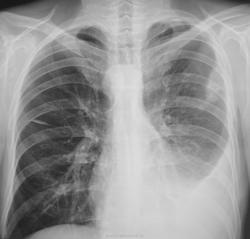

Зацепили по "флюшке"...

Было высказано продположение о наличии специфического процесса. Была рекомендована консультация фтизиатра. Однако, обстоятельства распорядились в другом векторе. Пациент был госпитализирован в хирургическое отделение был пунктирован, проведено противовоспалительное лечение... и через две недели был назначен рентген-контроль.

После проведенного исследования вновь, повторно была рекомендована консультация фтизиатра. Однако, фтизиатры патологию своей не признали.